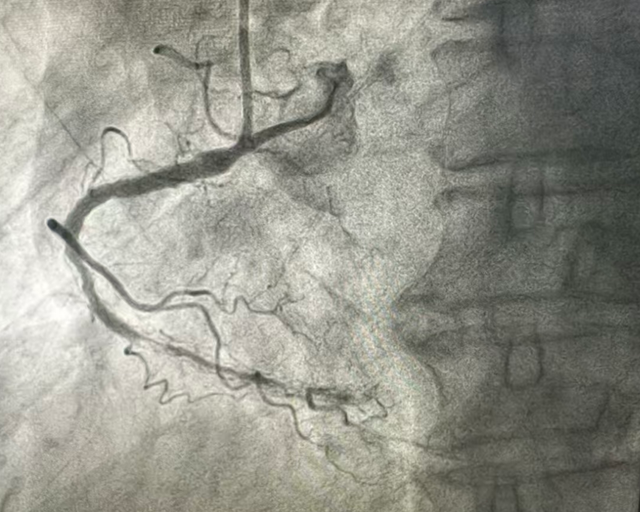

一周后,患者生命体征平稳、心功能及全身状况经优化调整达到可耐受手术状态后,及时为患者施行冠状动脉造影。

造影结果明确右冠状动脉原支架内完全闭塞:

精准评估病变特征后实施介入处理,通过球囊扩张成功重建支架内管腔,并进一步应用药物涂层球囊进行局部药物释放,以有效抑制内膜增生、降低再狭窄风险,体现了对复杂病变的精确干预能力。